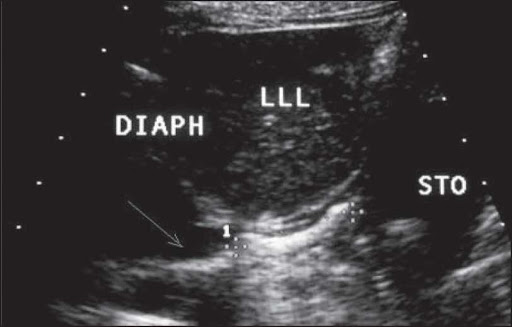

سونوگرافی شکم یک روش امن و بدون درد برای بررسی شکم است که در آن امواج صوتی به شکم فرستاده می شود و توسط کامپیوتری به تصویر در می آید. تصویر سیاه سفید به دست آمده محتویات داخلی شکم ( شامل آپاندیس, روده, کبد, کیسه صفرا, طحال, کبد و مثانه) را نشان می دهد.

در این نوع سونوگرافی اندازه ی ارگان های شکم و وجود آسیب یا بیماری در آنها مشخص می شود.

نوزاد روی تخت دراز می کشد و پزشک ژلی شفاف را بر روی پوست شکم می ریزد و پروب را بر روی آن قرار می دهد و به آرامی حرکت می دهد. امواج صوتی از پروب و از طریق ژل به شکم وارد می شود و توسط کامپیوتر به تصویر در می آید. د